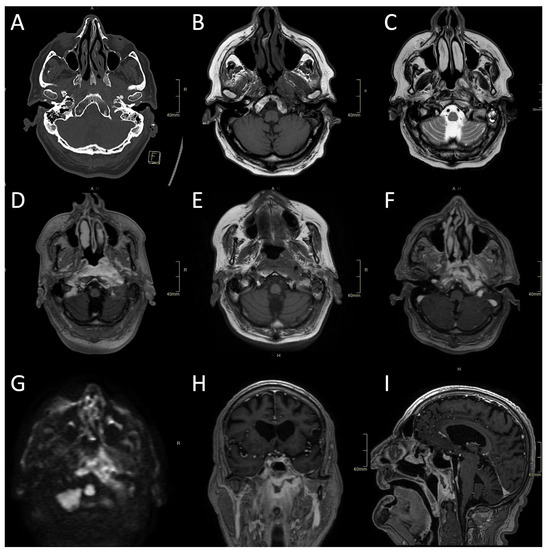

Figure 2.

CT and MRI of a fungal atypical skull-base osteomyelitis patient. (A) Axial CT bone algorithm reconstruction showing subtle cortical erosion of the left skull base and the left carotid canal; F—foot. (B) Axial MRI T1 showing subtle asymmetrical hypo-intensity, indicating oedema of the bone marrow on the left side of the clivus. (C) Axial MRI T2 showing asymmetrical hyperintensity in pharyngeal soft tissues and prevertebral muscles, indicating oedema and inflammation. (D) Axial MRI T1 showing the progression of oedema of the bone marrow of the clivus six weeks later. (E) Axial CE MRI showing the progression of hyperintensity in pharyngeal soft tissues and prevertebral muscles and affected bone marrow. (F,H,I) Axial, sagittal, and coronal CE MRI T1 showing extensive inflammatory changes in skull-base bone marrow and soft tissues, with non-enhancing branching fluid collection—abscess in the pre-clival and para/retropharyngeal soft tissues after 11 weeks. (G) Axial MRI DWI showing increased signal in the central skull base. CT: computerised tomography; MRI: magnetic resonance imaging; CE: contrast-enhanced; DWI: diffusion-weighted imaging.